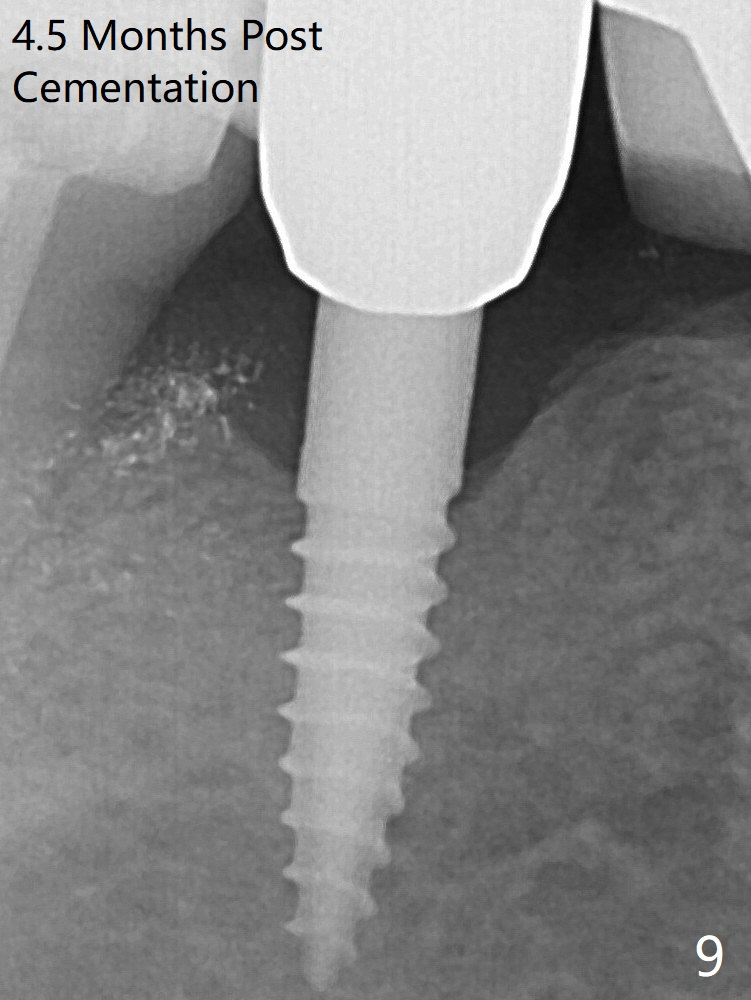

In fact the crown at #30 is redone because of loose proximal contact with #31; there is no bone resorption 13 months post cementation (Fig.11). The crestal bone loss is observed 3 months postop (Fig.6 arrowheads), as related to ridge reduction (cortical bone). Since then, there has been no bone resorption.